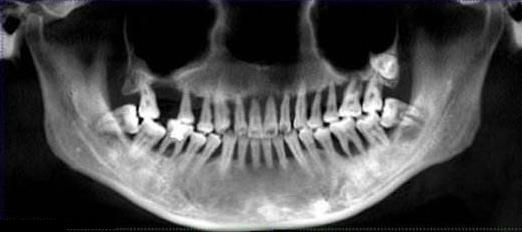

比如,之前有一位20多歲的小夥(huo) 子,全口嚴(yan) 重的牙周炎,牙槽骨嚴(yan) 重萎縮,等到醫院拍片時,多數的牙齒治療已經沒有價(jia) 值了,需要進行拔牙。

這就是典型的還沒來得及治療,牙齒就沒了的情況。

嚴(yan) 重牙周炎需要拔牙的牙片